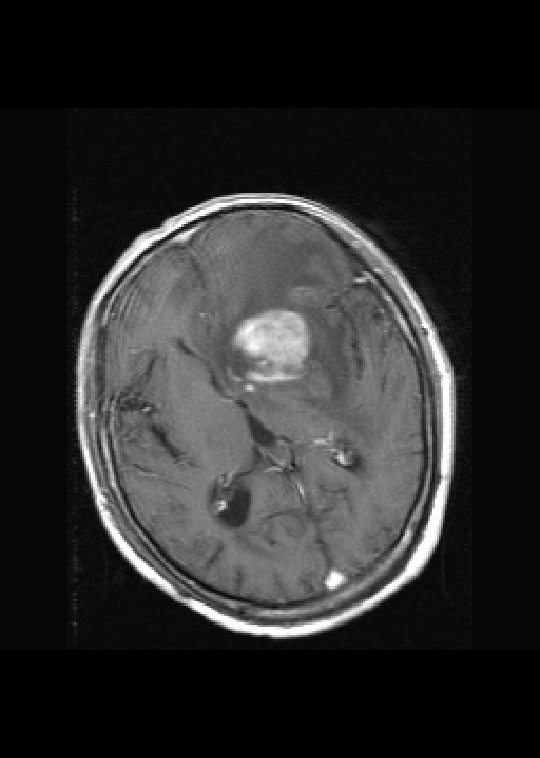

左侧基底节区病灶t1wi呈不均匀稍低信号,t2wi呈稍高信号,周围伴有水肿。增强扫描呈均匀团块样或者抱拳样明显强化,相邻的柔脑膜亦见线样强化。首先考虑淋巴瘤。可惜没有ct平扫,如果ct平扫病灶呈高密度,那么更支持pcnsl的诊断。

左侧基底节区长t1长t2异常团块状信号,增强呈明显均一强化,水肿明显,挤压侧脑室前脚,本人考虑为胶质瘤可能性大。

首考淋巴瘤,不太支持胶质瘤。

左侧基底节区病灶t1wi呈不均匀稍低信号,t2wi呈稍高信号,周围伴有水肿。增强扫描呈均匀团块样或者抱拳样明显强化,首先考虑淋巴瘤。